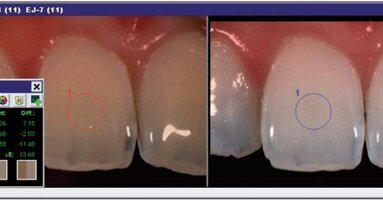

While most studies of whitening strips focused on tooth enamel, which contains very little protein, the current studies focused on dentin, which contains high levels of protein, most of which is collagen. Previous work has shown that hydrogen peroxide can penetrate the enamel and dentin, and that collagen in the dentin layer decreased when teeth were treated with whitening strips. “We sought to further characterize what the hydrogen peroxide was doing to collagen,” said Dr. Kelly A. Keenan, Associate Professor of Chemistry and of Biochemistry/Molecular Biology at Stockton University School of Natural Sciences and Mathematics. “We used entire teeth for the studies and focused on the impact hydrogen peroxide has on the proteins.”

In the new study, the researchers demonstrated that the major protein in the dentin is converted to smaller fragments when treated with hydrogen peroxide. In additional experiments, they treated pure collagen with hydrogen peroxide and then analyzed the protein using a gel electrophoresis laboratory method that allows the protein to be visualized.

“Our results showed that treatment with hydrogen peroxide concentrations similar to those found in whitening strips is enough to make the original collagen protein disappear, which is presumably due to the formation of many smaller fragments,” Keenan added.